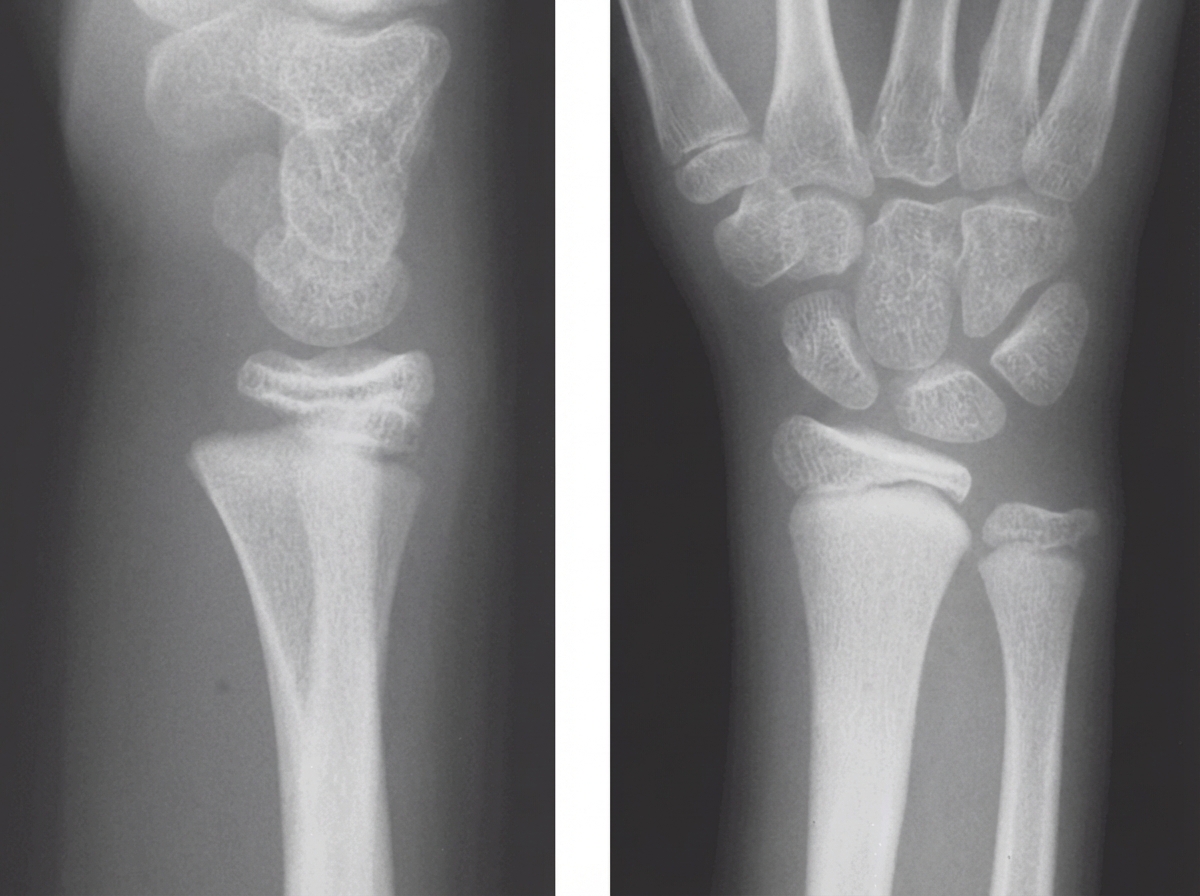

A 6-year-old refugee with delayed growth and weakness is brought to the physician. Her family has been displaced several times over the last few years, and nutrition and housing were frequently inadequate. Examination of the lower limbs shows bowing of the legs with reduced proximal muscle strength. The abdomen is protruded. Inspection of the chest shows subcostal grooving during inspiration. An image of the patient’s wrist is shown. Which of the following is the most likely cause of this patient’s condition?